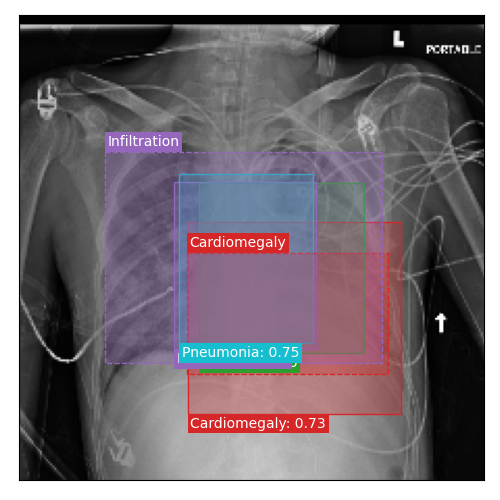

Qualitative Results

As shown in Fig. 4 Loc-ADPD detects cardiomegaly almost perfectly, as it is always exactly localized at one anatomical region. Other pathologies are detected but often with too large or too small boxes as they only cover parts of anatomical regions or stretch over several of them, which cannot be completely corrected using WBF. Detection also works well for predicting several overlapping pathologies. For qualitative comparisons between Loc-ADPD and MIL-ADPD, we refer to Appendix 0.B.

Appendix 0.B Qualitative Results and Failure Cases

| Loc-ADPD | MIL-ADPD | Loc-ADPD | MIL-ADPD |

![]() |

| (a) | (b) | ||